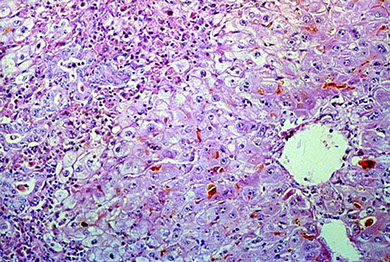

Micro: Swollen and necrotic hepatocytes (balloon degeneration) c steatosis, Mallory bodies, zone 3 fibrosis and neutrophilic infiltrates

- Mallory bodies: intracytoplasmic eosinophilic inclusion bodies, stain c intermediate filament, CK8/18, p62, and ubiquitin; in hepatocytes caused by ubiquinated cytokeratin intermediate filaments

Alcoholic hepatitis

Seen in constant long-term alcoholics

Alcoholic steatohepatitis with (1) steatosis (>5%), inflammation, and hepatocyte injury. This image shows all classic features of alcoholic steatohepatitis in a patient with a history of alcohol abuse. Macrosteatosis is obvious and two ballooned hepatocytes are shown containing Mallory-Denk bodies (top and bottom arrows). The arrowhead shows hepatocellular inflammation.